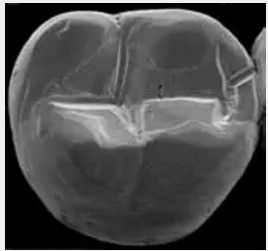

復(fù)合樹脂在即刻充填后,觀察其在電子顯微鏡下的掃描圖像,本次研究選擇了9種具有代表性的復(fù)合樹脂材料。

2.png

IPS Empress Direct Ivoclar Vivadent義獲嘉維瓦登特